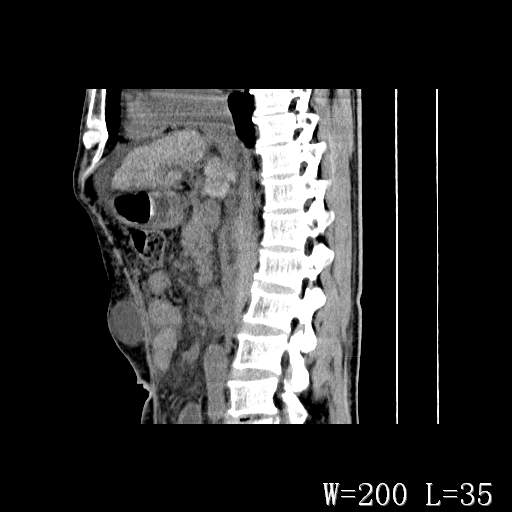

男,52岁,门脉高压断流术后1年,发现腹部肿物2月。

1)前腹壁中线区(脐上方)囊性占位性病变,考虑淋巴囊肿。2)腹水。